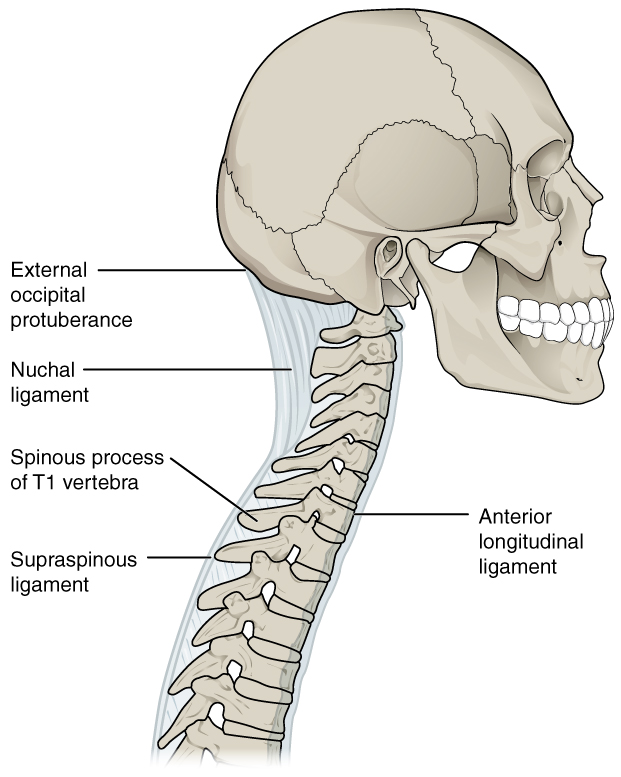

Https www alamy de bulletin der naturlichen histort museum geologie serie s andrews und y fernandez jalvo abb 16 a menschliche achse wirbel m 54042 zeigt die konformation des cut markierungen entlang der vorderen oberflache dies ist der bereich der befestigung der vorderen langsband und daruber hinaus die superior markierungen sind wahrscheinlich auf die ablosung der achse von der atlas und die hinteren markierungen aus um die loslosung der achse von der dritten halswirbel x 12 b schematische zeichnung des menschlichen schadel und oberen wirbel angezeigt um die disposition der beiden muskeln die an der inneren oberflache o image233869895 html (Dateityp jpg)

Bulletin Der Naturlichen Histort Museum Geologie Serie S Andrews Und Y Fernandez Jalvo Abb 16 A Menschliche Achse Wirbel M 54042 Zeigt Die Konformation Des Cut Markierungen Entlang Der Vorderen Oberflache